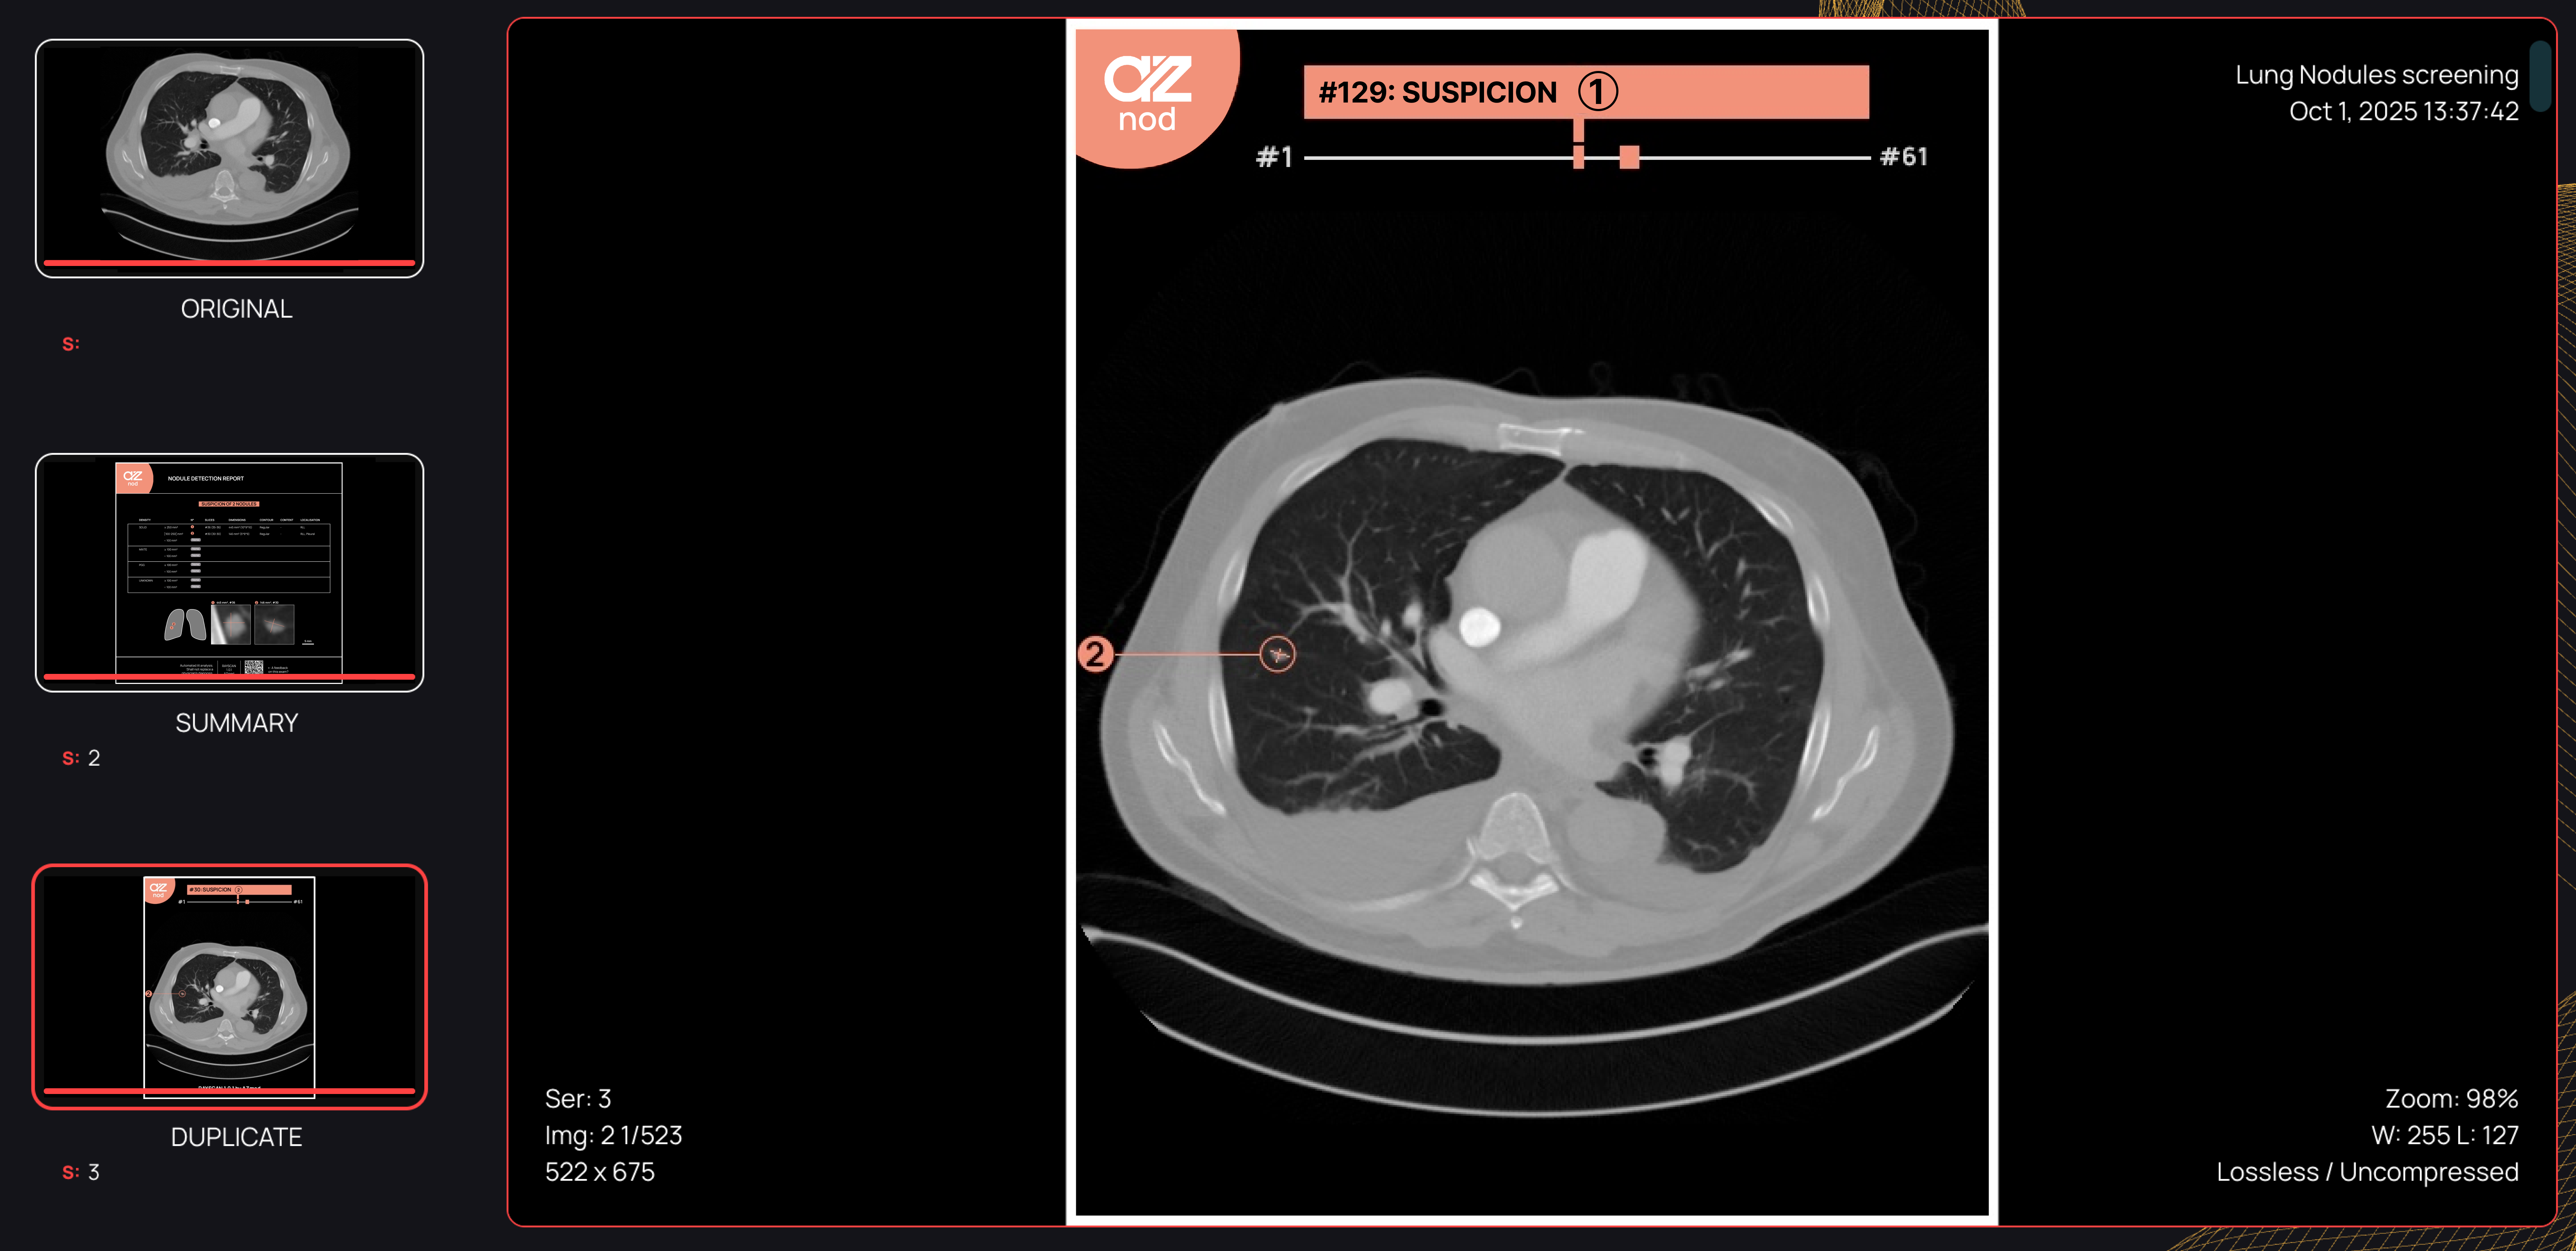

AZnod is designed to aid lung cancer screening programs by providing standardized detection and comprehensive characterization of pulmonary nodules on CT scans.

AZnod analyzes each slice of a CT to identify nodules between 3 mm and 30 mm. The system evaluates them, provides measurements of volume, long-axis diameter, and perpendicular diameters, and indicates the exact CT slices where they appear. It then classifies the detected nodules according to density, contour morphology, internal composition, and positioning in the lungs, which supports guideline-aligned clinical assessment without changing existing diagnostic workflows.

The AI model processes images that are strongly pseudonymized and returns structured radiology output to the user. The system provides a single report listing each nodule by clinical priority, with annotated views of size and standardized measurements in millimeters and cubic millimeters, along with its diagnostic attributes, as well as an anatomical lung schematic intended to allow rapid review in the assessment of nodules.